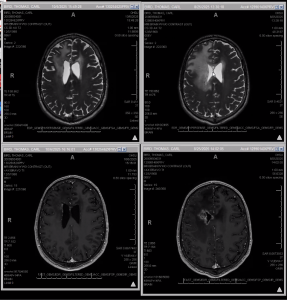

Tom had his last scan on 1/16 and the great news was it was unchanged and ruled stable. Unfortunately on Wednesday 1/28 Tom had his worst seizure yet while he was on a video call with his new counselor. He fell to the ground and was unable to respond. I was teaching Zumba and his counselor couldn’t reach me so he called 911. Tom was able to get up as the paramedics arrived and put Olive away but was still out of it and took him to the hospital. They were able to use Tom’s phone to call me which broke my do not disturb setting and I was able to leave. Our good friends and Portland family Jeff and Darrell came to meet us at the hospital. They did a CT and MRI, which they ruled unchanged so we once again do not know what brought on this seizure but it was definitely the longest most severe one Tom has had. We know it was not brought on by him being tired as he had just logged his best night of sleep ever per his Oura ring. We had a great day leading up to it and really felt like we had a handle on things so this last one, particularly the severity of it has us frustrated and depressed, not to mention that Tom has some injuries from his fall. We are very thankful he was on the call and that it was not worse, but we are still reeling. We are so grateful that so many of our wonderful friends have dropped by to see us and lift our spirits the last few days and bring food by. Our community is amazing and we are deeply grateful.